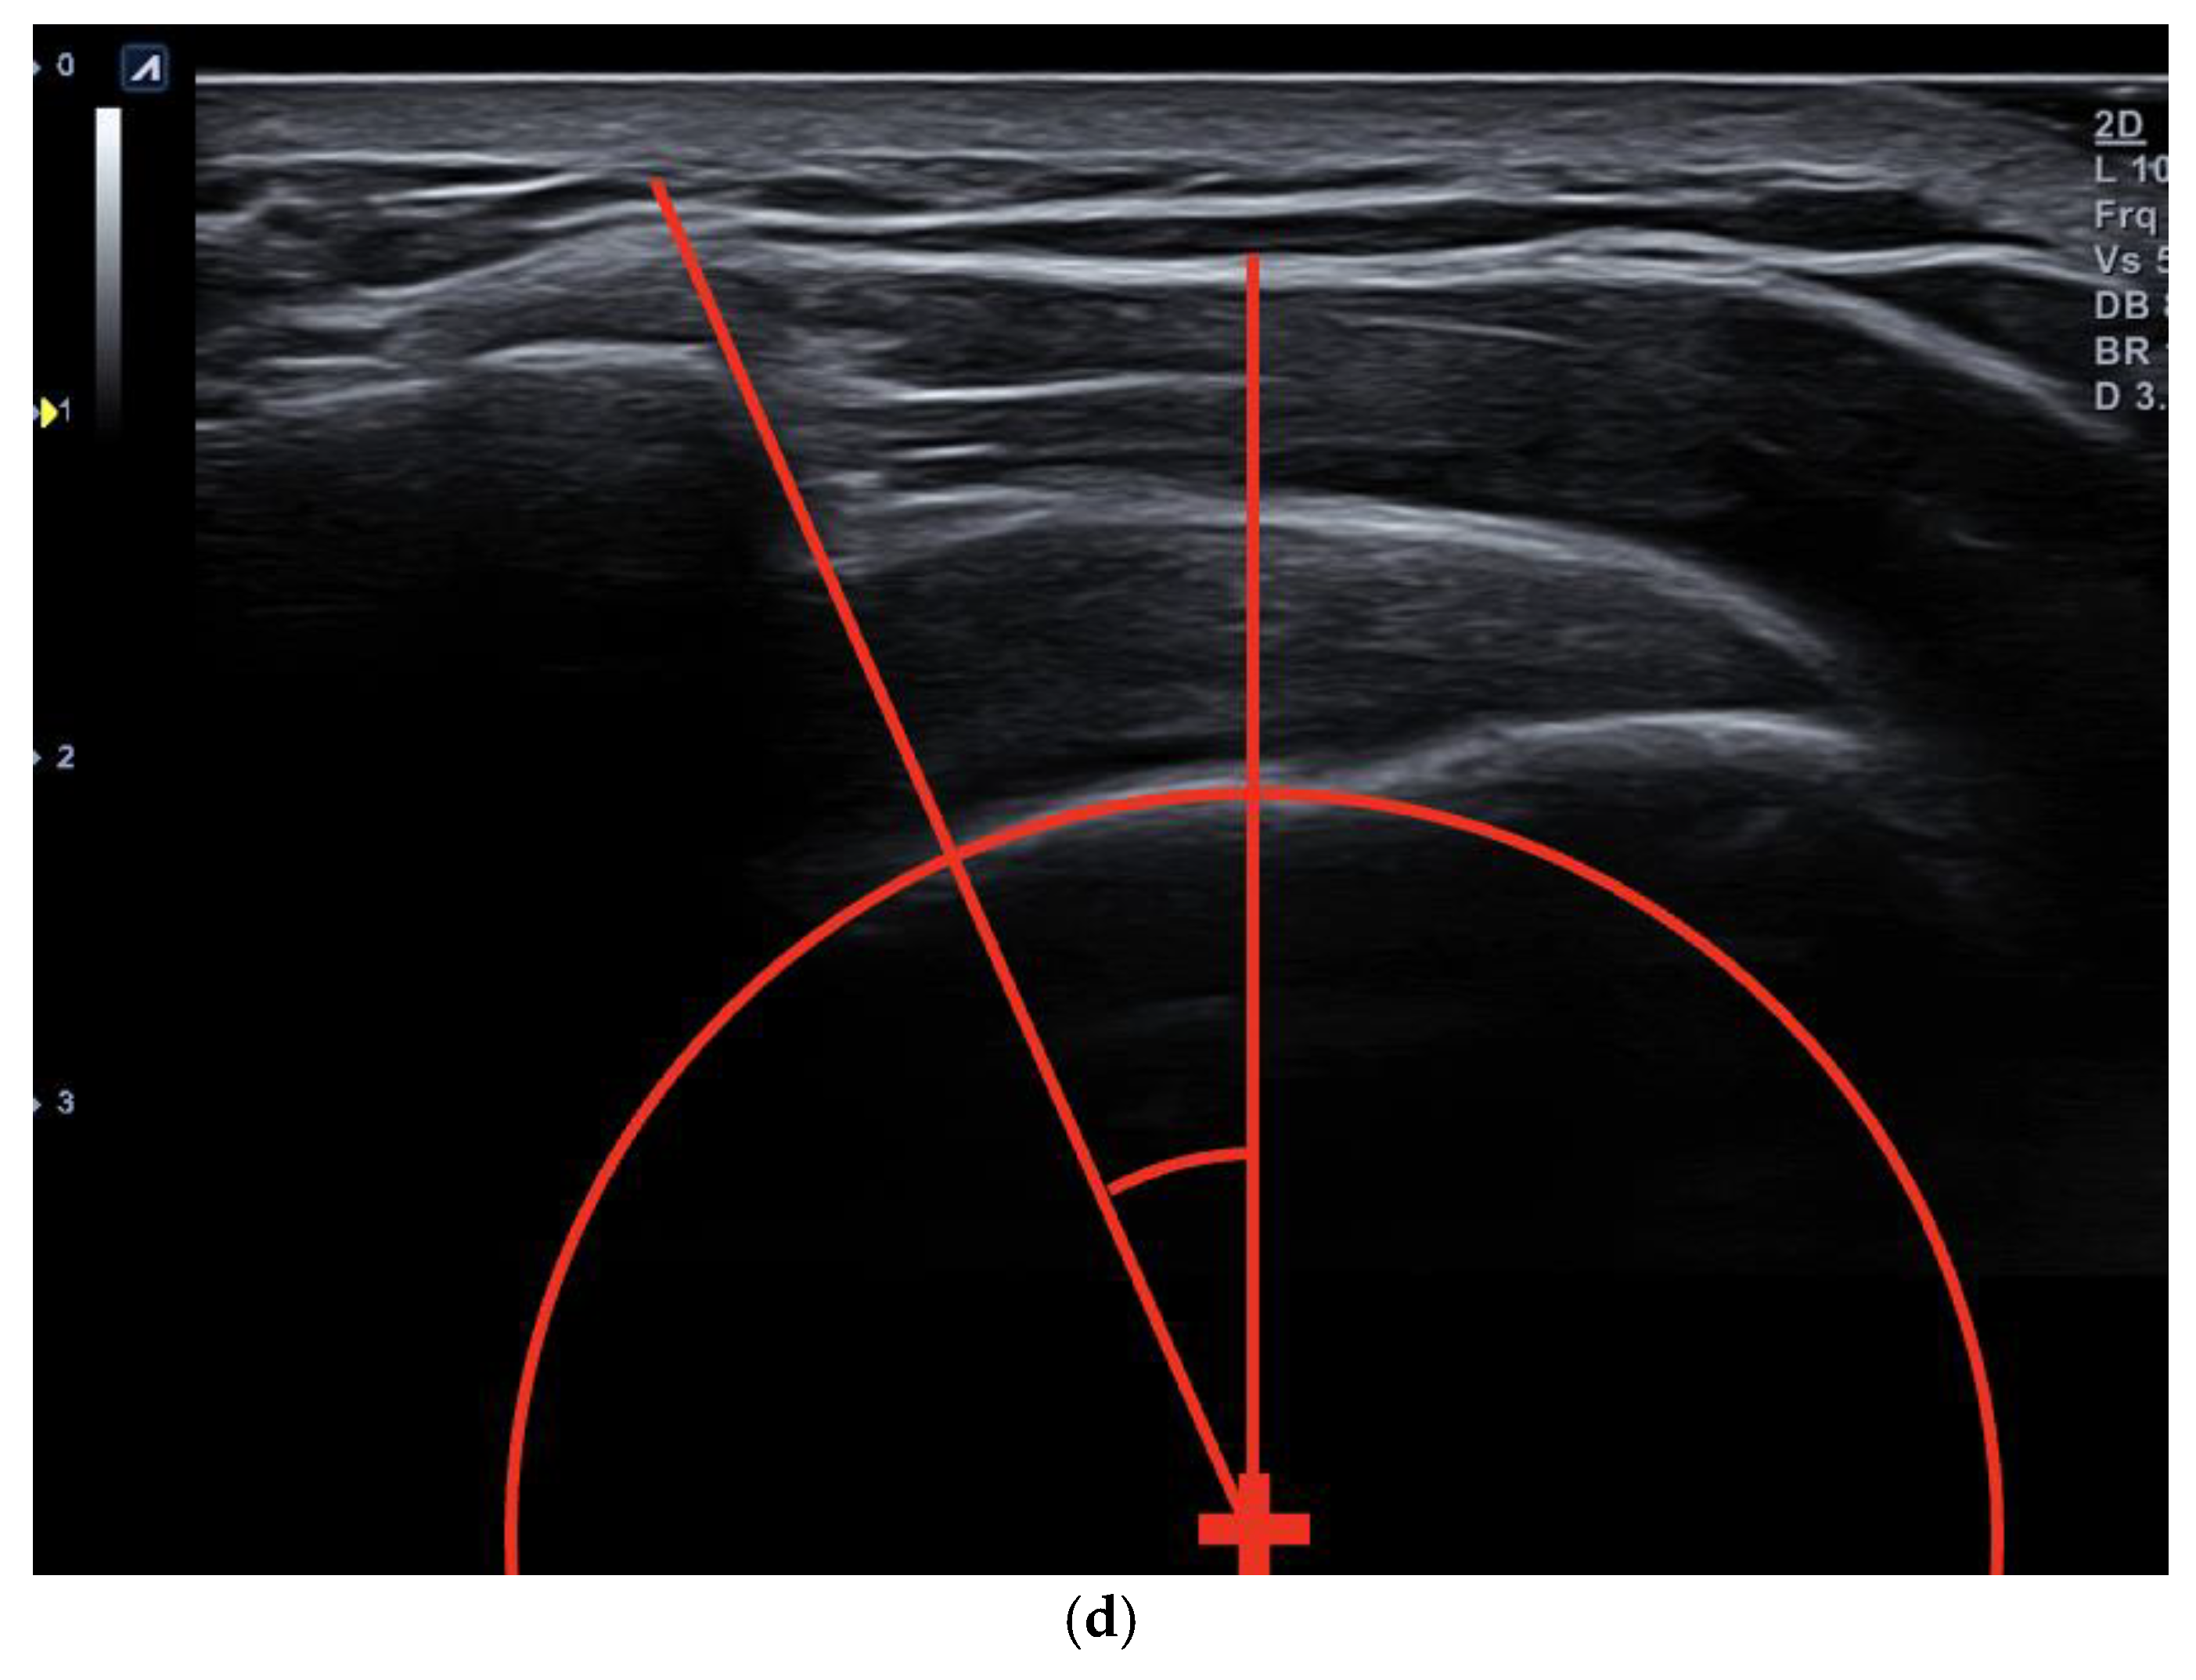

- Following this, a systematic approach was employed to position the first arm vertically up to the identified center of the humeral head and perpendicular to the horizontal borders of the monitor (Figure 3d).

- The second arm, originating from the circle’s center, was extended to the most lateral edge of the visualized acromion (Figure 3d).